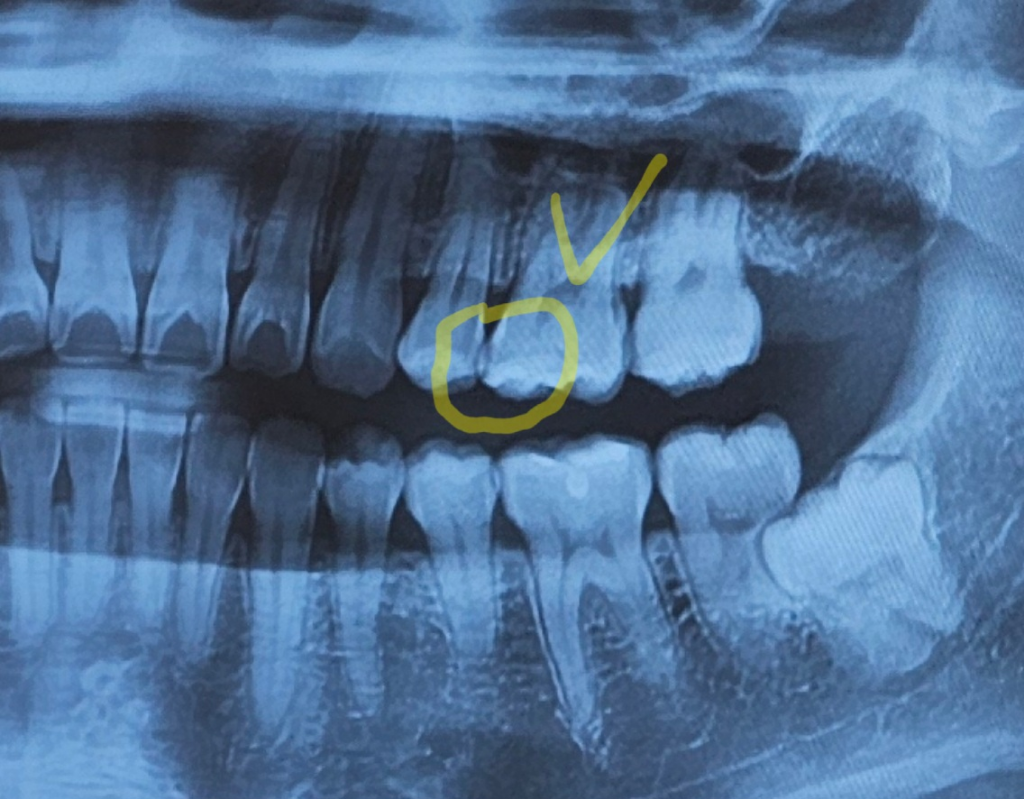

해당 사진은 panorama 사진으로 사진 상에서 치아가 겹쳐 보여 정확히 충치가 있는지 확인이 어렵습니다. 이러한 경우에는 해당 부분에 대한 정밀한 x-ray 사진 촬영이 필요하며 임상 검사도 더불어 이뤄져야 합니다. 지금 사진으로는 명확한 답변을 드리기 어렵습니다.

엑스레이 상으로 치아가 겹쳐 잇어서 정확하게 보이진 않지만, 저상태라면 인접면에 약간 충치가 잇는것처럼 보이긴합니다.

사진으로만 봤을 경우에는 인전 면에 방사선 투과성이 보이긴 합니다. 인접면 충치가 있을 수 있지만 실제 충치의 여부는 정확하게 확인을 해봐야 알 수 있을 것으로 생각됩니다.

인접면 충치의 경우 파노라마 사진에서는 치아끼리 겹쳐 보이는 경우가 있어서 판단이 어렵습니다 치근단 방사선사진(작은 x-ray) 중에서 교익 사진을 찍어 판단합니다

일단 주어진 파노라마 방사선 사진에서는 아주 큰 충치는 아닌것으로 보이긴 합니다

방사선사진을 캡처한 사진이다 보니 화질이 좋지 않아 정확한 진단은 무리가 있으나, 체크하신 치아 mesial(안쪽)면과 그 앞쪽 치아 distal(먼쪽)면에 인접면 충치가 의심됩니다. 검진받으신 치과 선생님께서 방사선사진 검사 및 임상 검사를 하시고 수립하신 치료계획이니, 그 계획대로 치료 받으시면 무리없을 것으로 보입니다.